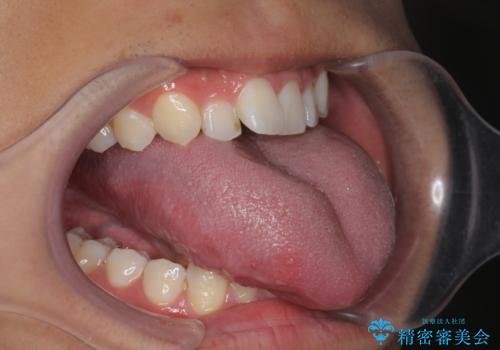

舌小帯切除術を行い舌の可動域を広げました。

舌の可動域は広がりますが舌の訓練を行わないと滑舌は良くなりません。